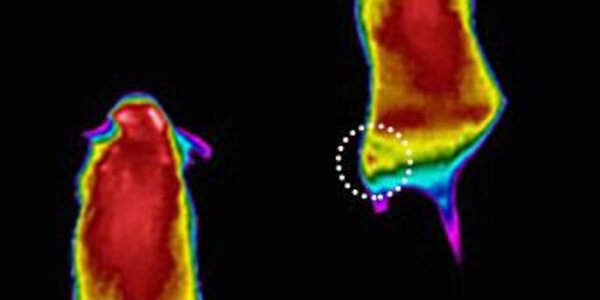

The Teenage Brain on Drugs

One way to look at addiction is to consider it a form of learning, a type of learning that is extremely effective in its ability to affect the adolescent brain, report researchers working under an NIH grant. The maturation process of the brain may cause teens and young adults to become addicted faster than older adults, because the impulse control centers of the brain are not fully developed in the younger cohort. Drugs not only interfere with the normal processing functions of the brain, they actually change both the structure and function of the brain. Over time, drug use and abuse can…